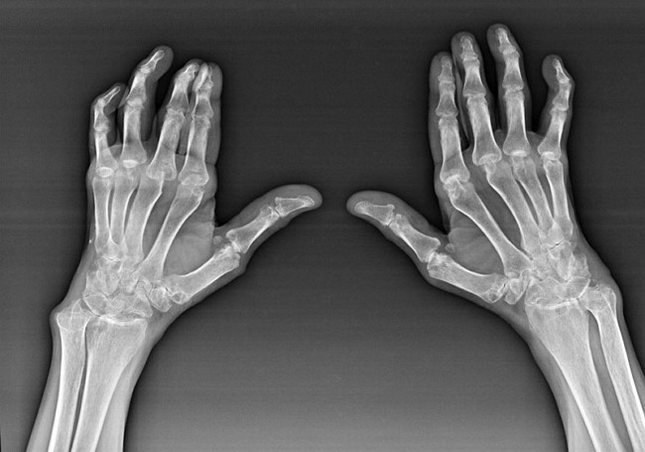

Revmatoidní artritida je onemocnění, při kterém lidský imunitní systém poškozuje vlastní tkáně těla. Jinými slovy, revmatoidní artritida je autoimunitní patologie. Toto onemocnění je také systémové, protože s ním je ovlivněno mnoho tkání (Svaly, klouby, plavidla atd.) a orgány (Srdce, ledviny, plíce atd.) v těle.

Navzdory skutečnosti, že revmatoidní artritida je systémovým onemocněním pod ní, ve větší míře trpí klouby, zatímco léze jiných tkání a orgánů je v pozadí. S touto chorobou může být ovlivněno téměř všechny typy štětcových kloubů (náramky, karpální cesty, metakarpal-phalanga, meziflační klouby). Léze je obvykle symetrická (ty. Ovlivněny jsou stejné klouby) na obou rukou, doprovázený otokem, bolest v poškozených kloubech. Ráno, během zvedání z postele, je v postižených kloubech nějaká tuhost, která může trvat asi 1 hodinu a poté zmizet bez stopy.

Poměrně často s revmatickou artritidou poblíž postižených kloubů štětce (častěji klouby pianofalanx, mezifalský) Se objevují revmatoidní uzly. Jsou to zaoblená formace umístěná pod kůží. Na štětci tyto formace vyvstávají nejčastěji na zadní straně. Na palpaci jsou husté, neaktivní, bezbolestné. Počet z nich se může lišit.